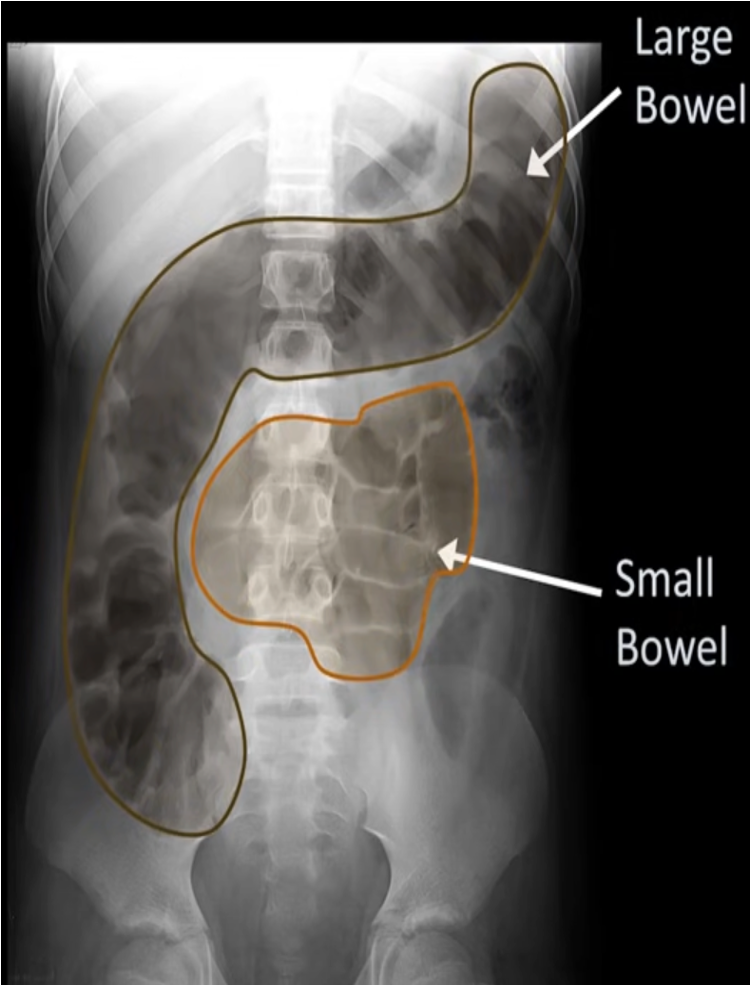

Normal bowel gas pattern

Normal supine AXR

Location of large bowel

Small bowel enlargement (Valvulae conniventes)

Large bowel Haustra

Small bowel (Valvulae conniventes)